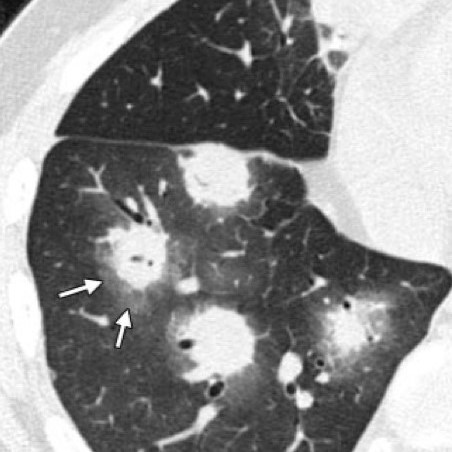

Визуализация и диагностика неинвазивного аспергиллеза с помощью КТ

Раздел: Необычные решения